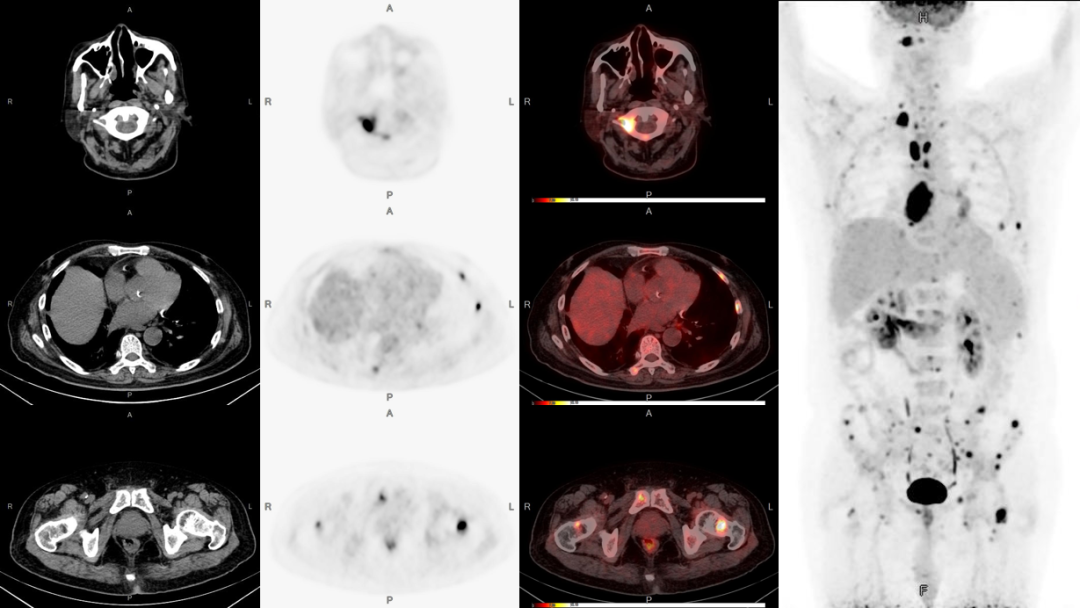

PET/CT是利用正電子核素標記葡萄糖顯示來反映病灶的代謝變化和解剖學結構的一種核醫學成像設備。

PET/CT整合了正電子發射斷層顯像和X射線斷層掃描兩種影像技術的優點,能從分子水平反應腫瘤的生理、病理、生化和代謝變化,被譽為“癌癥早篩利器”。

早發現。PET/CT能早期診斷腫瘤等疾病。在腫瘤早期尚未產生解剖結構變化前,即能發現隱匿的微小病灶。

安全無創。檢查所采用的核素大多數是構成人體生命的基本元素或極為相似的核素,且半衰期很短,所接受的劑量較一次胸部CT掃描的劑量稍高,安全高效。

結果精準。通過定性和定量分析,能提供有價值的功能和代謝方面的信息,同時提供精確的解剖信息。

快速全面。PET/CT一次全身掃描(頸、胸、腹、盆腔)僅需幾分鐘,就能分別獲得PET、CT及兩者融合的全身橫斷面、冠狀面矢狀面圖像,可直觀的看到疾病在全身的受累部位及情況。

●PET/CT為實現醫學影像學腫瘤診斷的“四定”(定位、定性、定量、定期)為診斷及治療奠定了可靠的基礎。

鑒別腫瘤的良惡性,提供全身器官和組織有無腫瘤轉移的信息,對腫瘤進行精準的臨床分期;

有利于查找腫瘤的原發病灶明確已有轉移灶;

腫瘤治療后的隨訪,及時指導臨床調整治療方案。